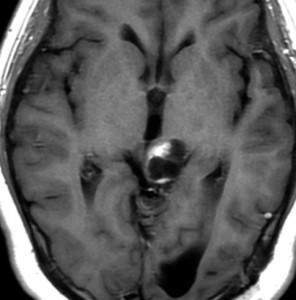

tectal gliomaに間違えそうなPPTID 松果体実質腫瘍

上段のガドリニウム増強MRIでは松果体腫瘍に見えやや境界が不明瞭なので,年齢からはPPTIDが疑われます。しかし,CISSの画像で,中脳上丘との境界がなく中脳腫大があるようにみえ,テクタールグリオーマを疑って経過観察しました。腫瘍がゆっくり増大したので摘出したところPPTIDという診断がつきました。